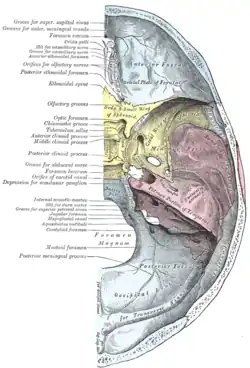

Base do crânio. Superfície superior.

Base do crânio. Superfície superior. -